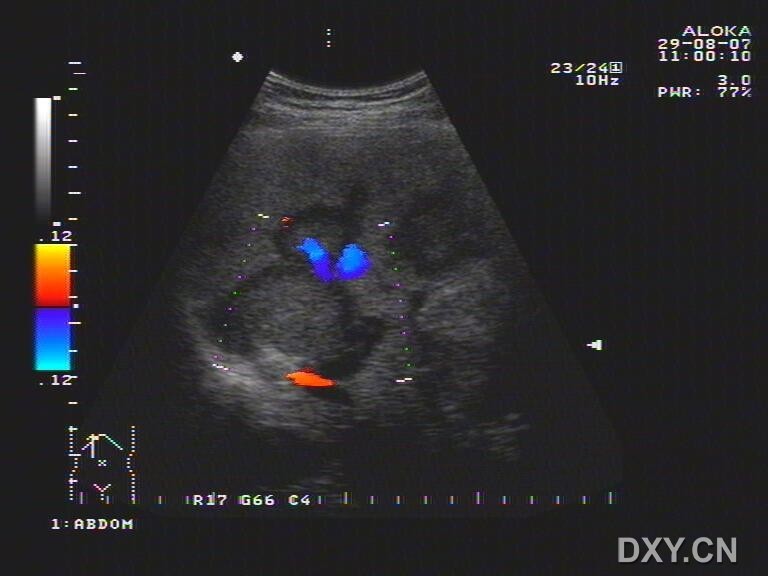

肝门部的混合回声团没想到竟然是这种肿瘤